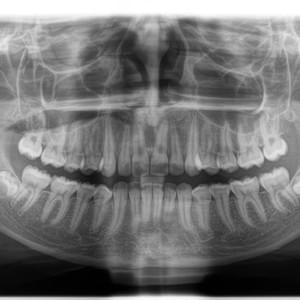

Panorámicas y teleradiografías para ortodoncia

Scanner Cone-Beam CT de última generación

Panorámicas, teleradiografias y CBCT con el sensor más moderno, preciso y de baja dosis.